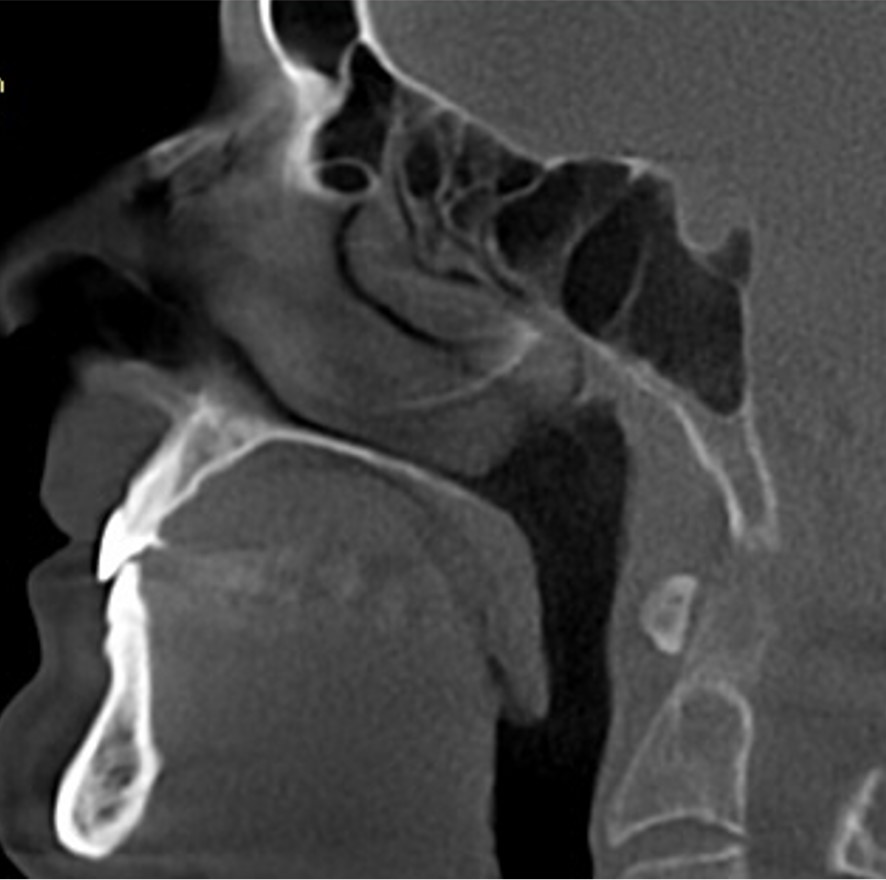

38 / 46

38) Identify the error in this CBCT image? (1 mark)